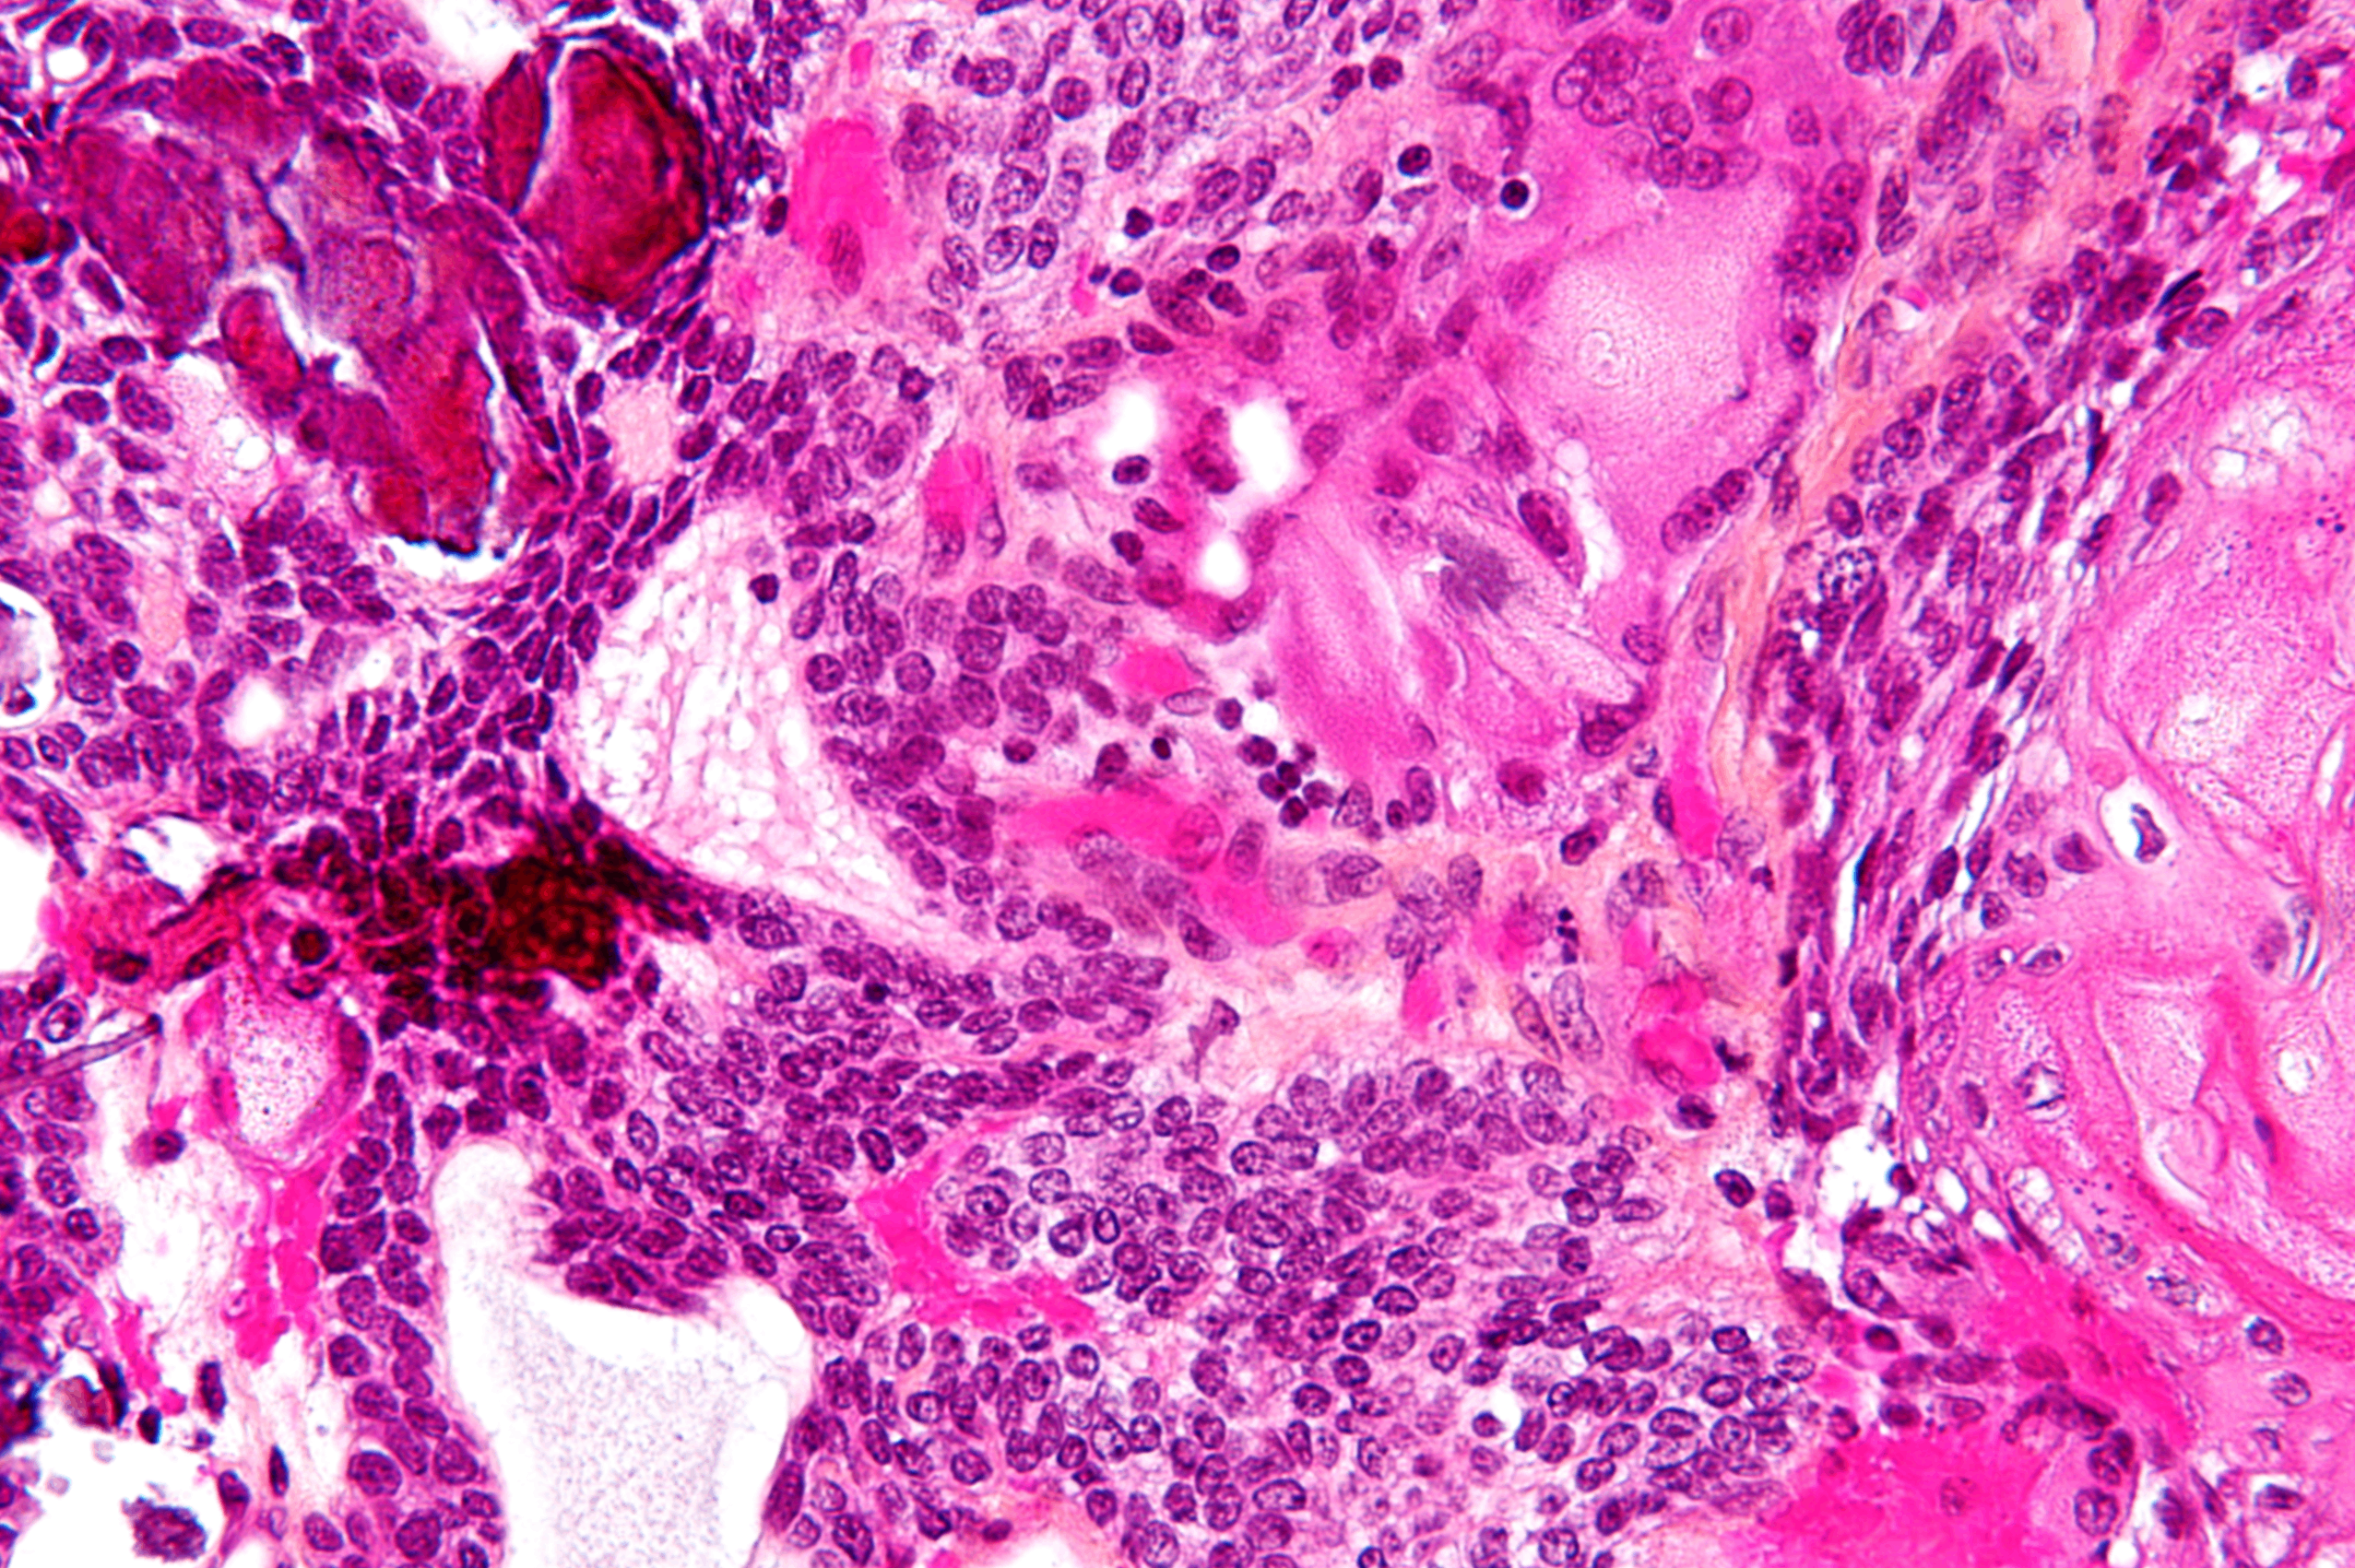

2) 병리소견 (Morphology)

낭성 또는 고형+낭성 혼합 병변이며, 내부에 탁하고 노란 색의 기름 같은 내용물이 차 있음

두 가지 조직학적 아형:

① Admantinomatous type (소아에서 흔함)

- 치아형태모양(adamantinoma-like) 세포 배열

- "기저세포 양상(basaloid palisading)", "습윤한 각질(wet keratin)", 석회화(calcification)

- 종양 주위로 염증 및 반응성 섬유화

② Papillary type (성인에서 흔함)

- 석회화 없이 유두 모양 성장을 보이며, 기저세포층이나 각질화는 관찰되지 않음